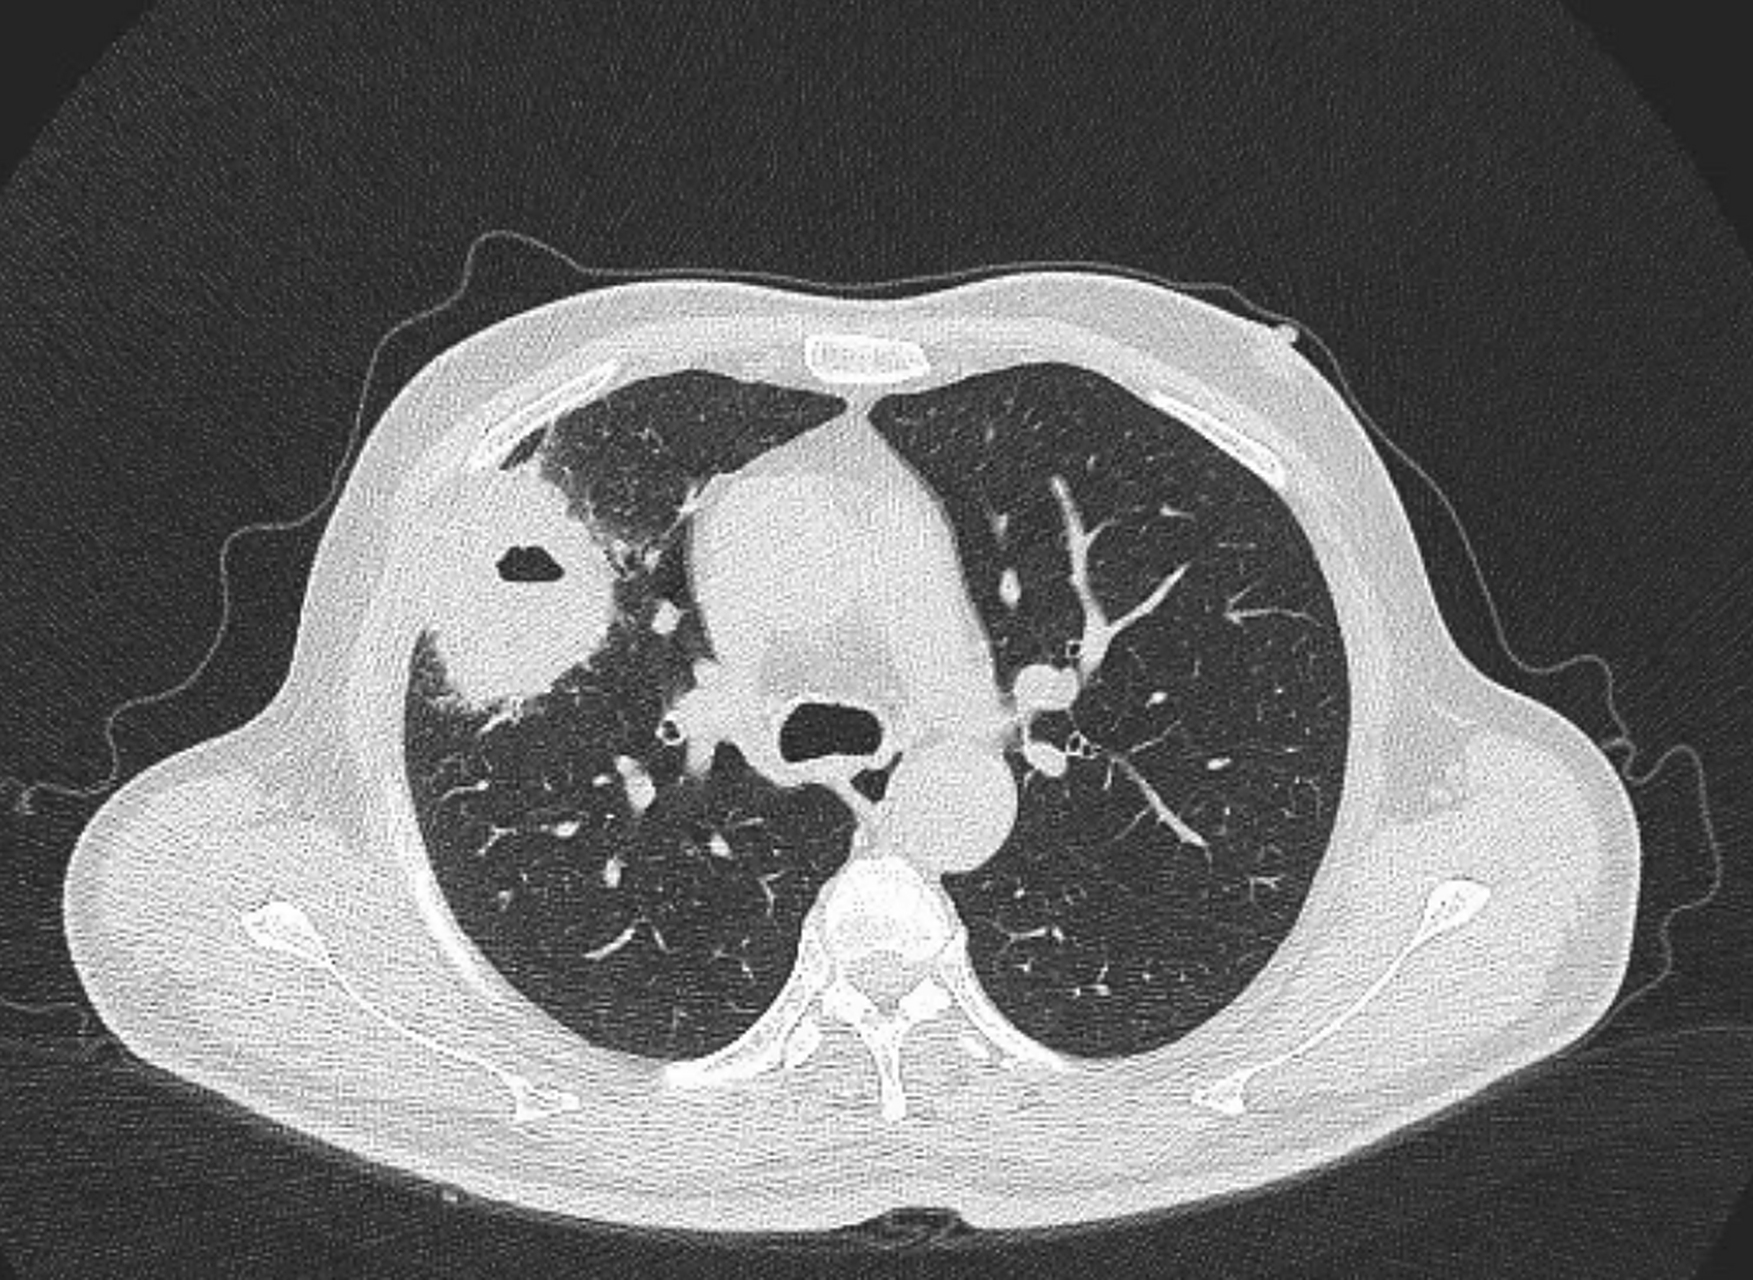

一个肺脓肿患者,差点被误诊为肺癌 这个病人50岁,咳嗽,咳痰四五天了

图片尺寸1753x1280